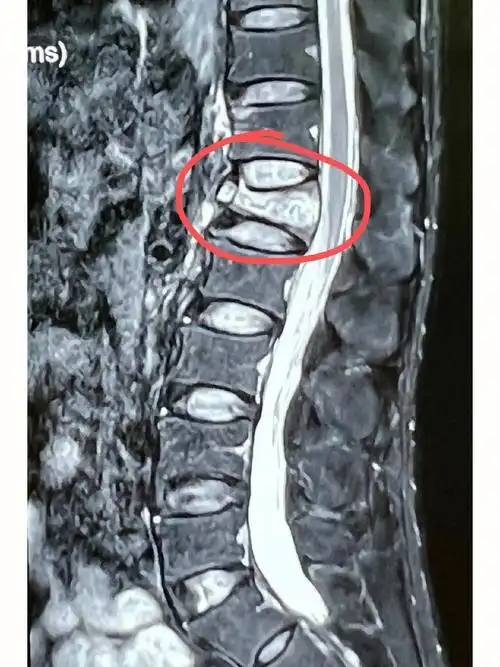

腰1椎体压缩骨折复位固定